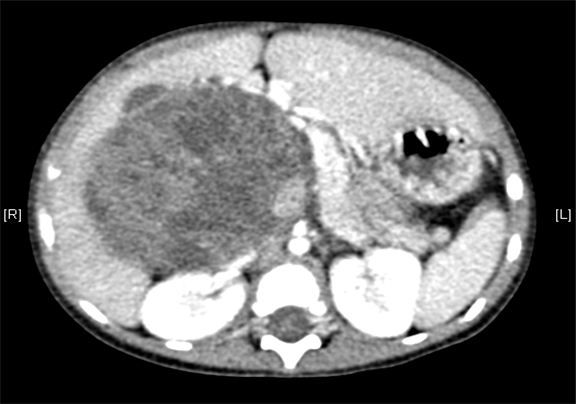

术后CT检查:

动脉期

静脉期

平衡期

术后病理提示肾母细胞瘤(上皮型)

术后给予抗炎、补液、止血等对症支持治疗。患儿恢复良好,无腹痛,伤口愈合好,无渗血渗液,于2016-2-14出院。